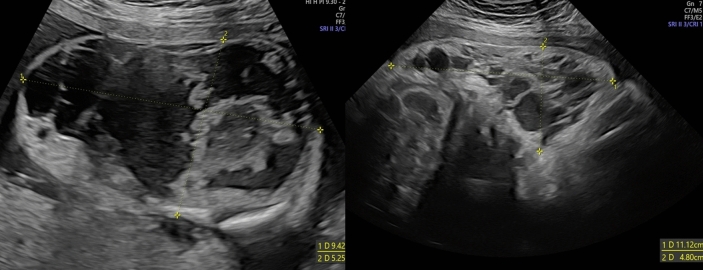

Case reports: Here we report two cases of effective prenatal and postnatal sirolimus treatment of extensive, complicated fetal CLVMs. The CLVMs were diagnosed prenatally by ultrasound and confirmed by magnetic resonance. The pregnancies were complicated with intralesional bleeding in both cases and polyhydramnios in one. The pregnant women received oral sirolimus from the 32nd and 33rd weeks of gestation to delivery (for 11 and 31 days, respectively). The dose of oral sirolimus for the pregnant women ranged from 2 to 6 mg/day, with a target trough whole-blood level of 7-12 ng/mL, which resulted in the umbilical cord arterial blood levels of 3.8 and 6.4 ng/mL, respectively. Therapeutic effects of prenatal sirolimus were observed in both fetuses: one experienced reduced intralesional bleeding, while the other had a significant decrease in CLVM size. The sirolimus treatment has been continued postnatally in both children, currently aged 20 and 9 months. The mothers and children experienced no adverse events from the treatment.